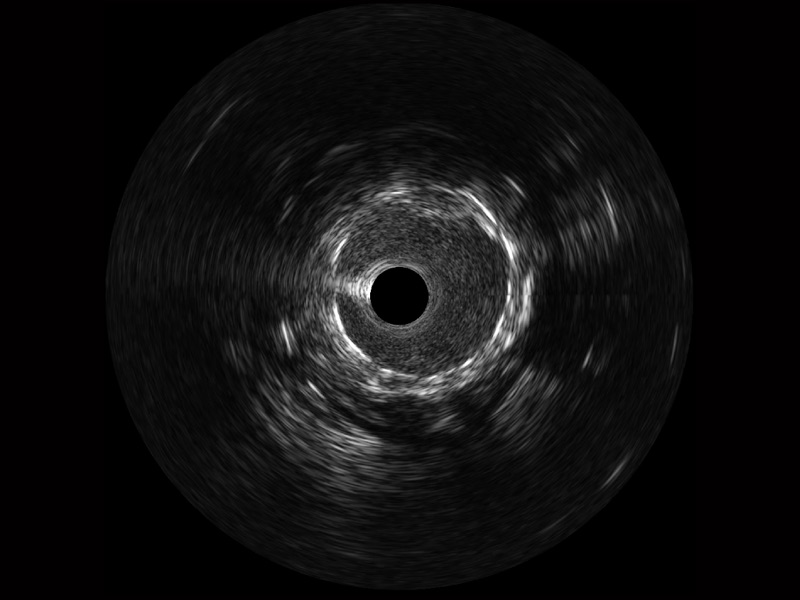

• 亚星官网宽频IVUS图像

• 传统IVUS图像

对比传统IVUS导管成像,亚星官网宽频IVUS图像的近场支架梁显影更细腻,远场中膜外血管仍清晰可辨,兼顾远中近,兼顾分辨力与穿透深度